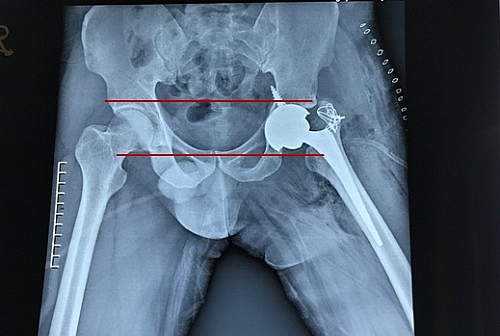

| Sau phẫu thuật ổ cối và đầu khớp đã nằm cân đối trên một trục. |

Bệnh nhân được phẫu thuật thay khớp háng toàn phần. Khó khăn nhất của ca mổ là phải tìm được ổ cối “thật” đã bị lấp đầy và biến dạng bởi các mô xương tái tạo để có thể tiếp nhận được khớp nhân tạo một cách vững chắc. Năm ngày sau ca mổ nhiều thử thách, bệnh nhân đã có thể đi những bước đi bình thường, không còn khập khiễng. Vùng ổ cối và đầu khớp háng đã cân đối.